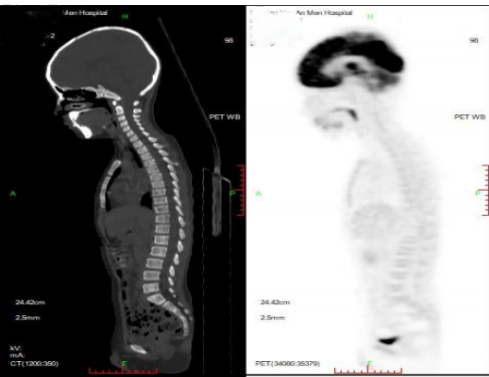

PET-CT(2023.05.12):

颅骨、颞面及左侧颞叶高密度影消失。

PET-CT(2023.09.15):左肾上腺区术后改变,术区未见肿瘤代谢活性病变,持续CR。

PET-CT(2024.11、2026.01):

未见代谢活性增高。